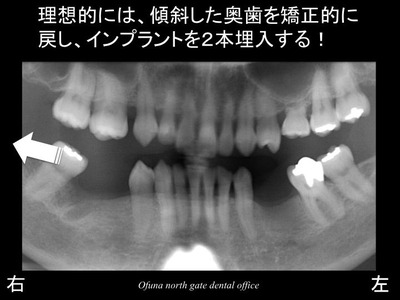

理想的なプランは、以下のようになります。

奥の傾斜している天然歯を矯正治療により起こします。

つまり真っすぐな状態に戻すのです。

そして、隙間を2歯欠損分にして、

インプラント治療を開始するのです。

この2歯欠損分が正常な状態ですから…